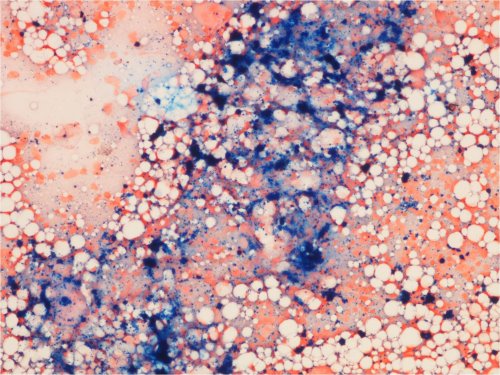

Luuytimen rautavärjäys

• Lapsen normaalissa luuytimessä on yleensä hyvin vähän kudosrautaa, ja rautavärjäys on negatiivinen.

• Kudosrauta on lisääntynyt ja siis rautaa nähtävissä luuytimen rautavärjäyksessä tiloissa, joissa kehittyy esim. transfuusiosideroosi.

• Kudosrautaa on nähtävissä luuydinbiopsiassa sekä stroomassa tippavärjäyslasin keskiosassa.

Kuva 36. Luuytimen rautavärjäys. Rauta (sininen väri) kerääntyy makrofageihin. Beetatalassemia major ja transfuusiosideroosi.

Kuva 37. Luuytimen positiivinen rautavärjäys. Potilaalla ALL ja kantasolusiirron jälkitila. 1) Kudosrauta (sininen väri) kertyy makrofageihin.